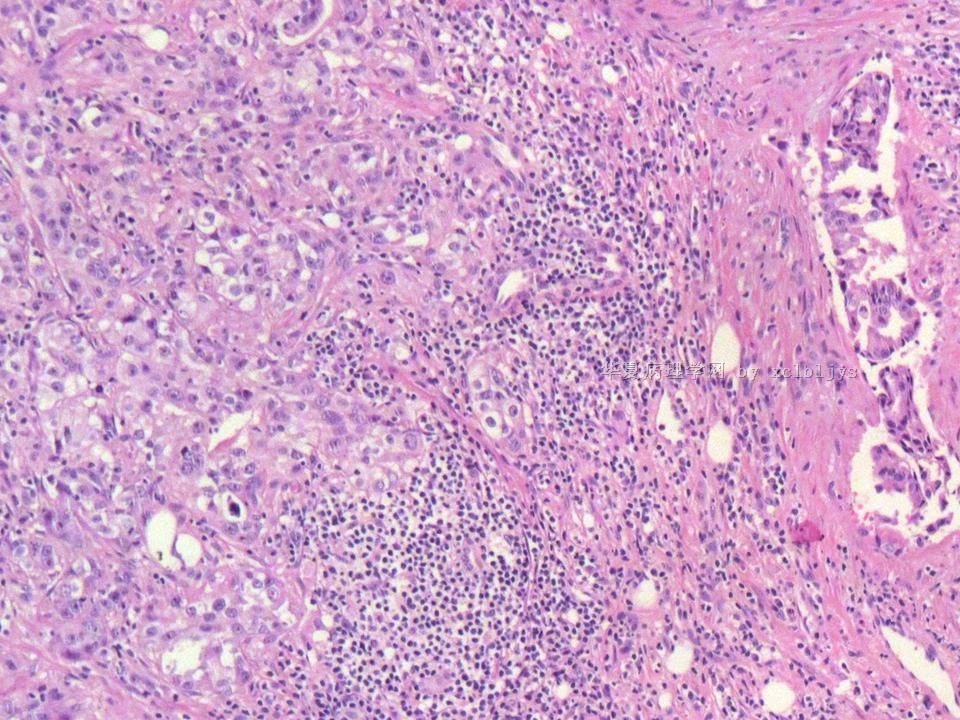

姓    名: ××× 性别:  男 年龄:  56

左锁骨上肿块三月余,手术切除。

蚕豆大肿块,包膜较完整,切面灰红色,质软。

• 左锁骨上肿块(IHC)图2

图2

转移癌

首先考虑甲状腺或肺来源

转移性腺癌。清查胃、肺等处有无原发灶。

转移性腺癌,请查消化道

免疫组化结果:TTF-1(+),CK7(+),CK20(-),TG(-)。临床近一步检查,肺未见肿块,左甲状腺发现肿块,目前仍未处理。

从形态结构看,有腺泡也有乳头结构,倾向转移性肺腺癌。